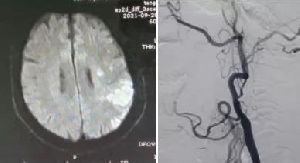

我院神經(jīng)內(nèi)科成功完成一例頸內(nèi)動(dòng)脈慢性閉塞再通術(shù)

近日,我院神經(jīng)內(nèi)科介入團(tuán)隊(duì)成功完成一例頸內(nèi)動(dòng)脈慢性閉塞再通術(shù)?;颊吣校?6歲,因“言語不清1天”于9月27日由外院轉(zhuǎn)入我院。既往“高血壓病”病史10余年,“冠心病心絞痛”病史2年?;颊呷朐汉箢i部血管彩超檢查示:左側(cè)頸內(nèi)動(dòng)脈閉塞;腦MRI檢查示:左側(cè)半球急性腦梗死。10月5日行全腦血管造影檢查示:左側(cè)頸內(nèi)動(dòng)脈起始處閉